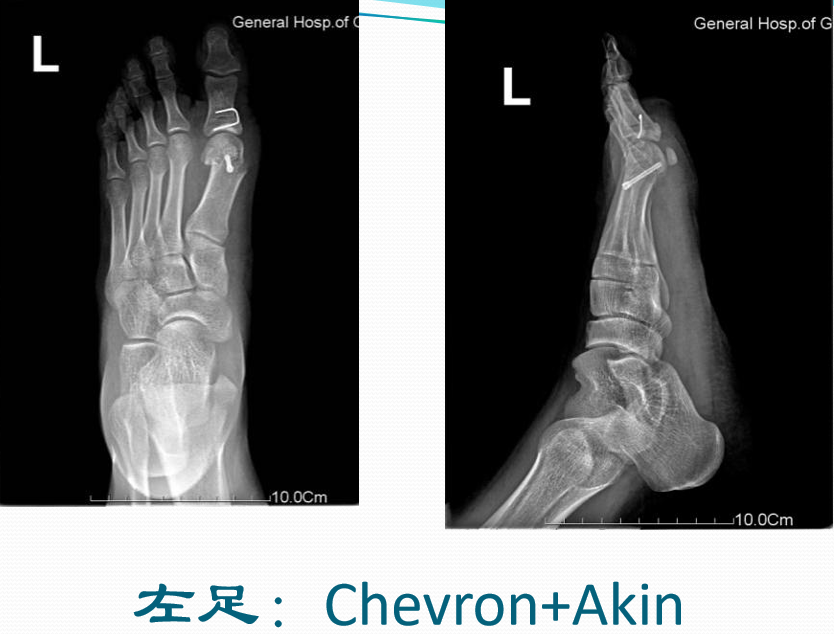

典型病例例1:姚X,女,78Y。

Chevron+第二跖骨Weil